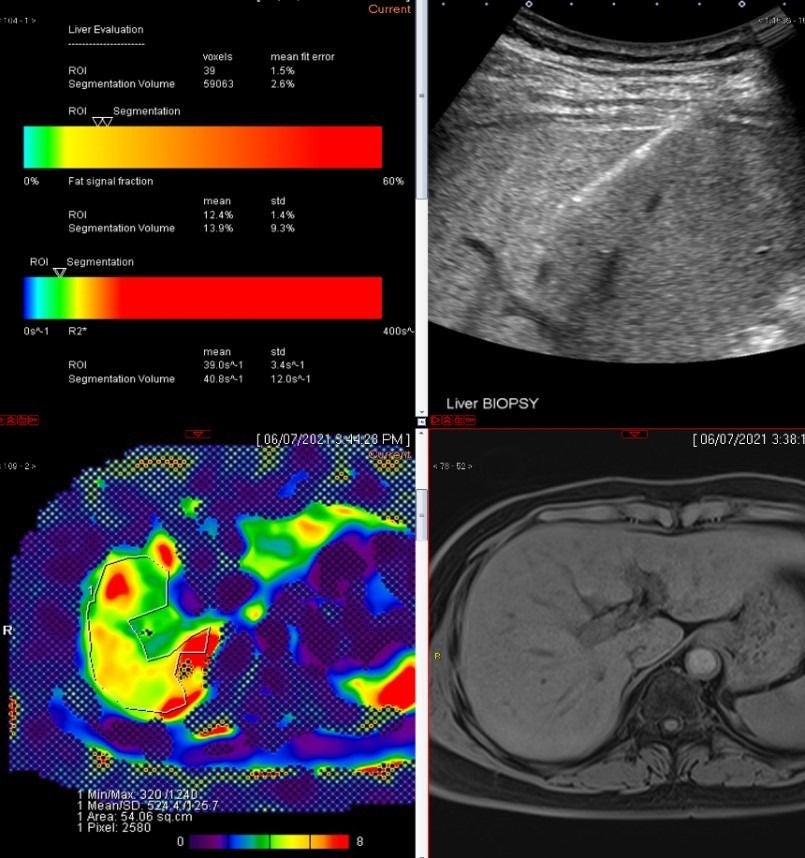

The specialists in the SGH Division of Radiological Sciences have diverse interests and expertise, and support or lead qualitative clinical and quantitative imaging research work over a wide range of imaging modalities applied to diseases of the brain, head and neck, spine, joints, breast, chest and abdomen in adults.